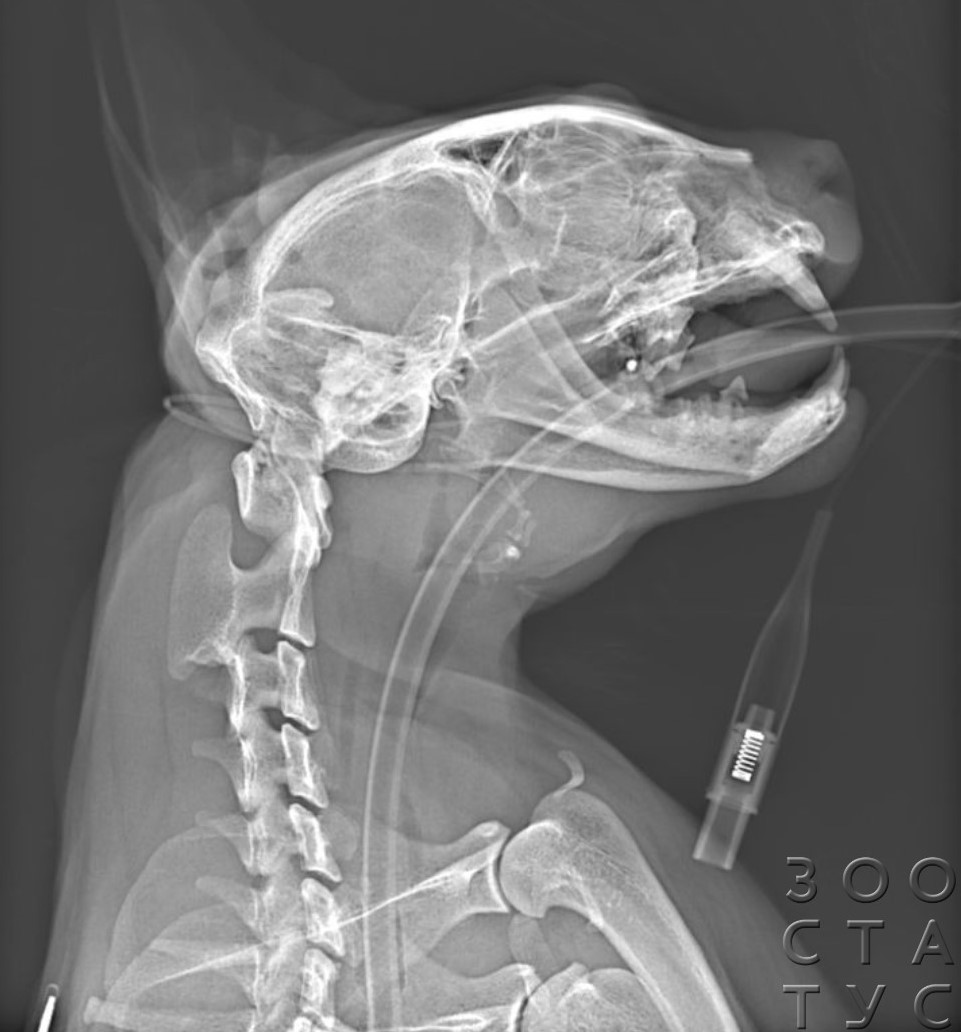

- после автотравм, падения с высоты - рентген позволяет не только выявить переломы конечностей у кошки, но и обследовать грудную клетку, вовремя выявив жизнеугрожающие травмы;

В некоторых случаях необходимо сделать несколько снимков - например, при политравмах может быть нужен и рентген головы, челюстей, рентген лап. Иногда для определения проблемы в желудочно-кишечном тракте проводят серию снимков с рентгеноконтрастным веществом. При некоторых травмах позвоночника показана миелография - введение контрастного вещества под оболочки спинного мозга.